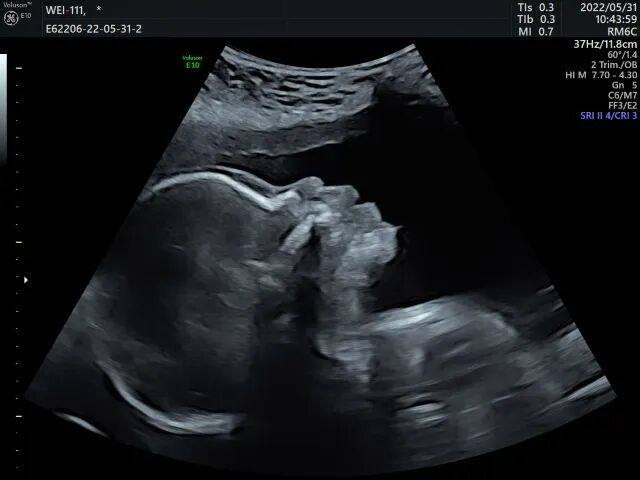

医学超声分为超声诊断和介入超声,介入超声又分为介入诊断和介入治疗。普通B超,是一种二维超声,图像是黑白的,能观测到胎儿的组织结构。

三维彩超是在二维超声的基础上,利用计算机再处理技术达到立体模式重建的超声诊断技术,能看到胎儿的立体图形。

四维彩超就像摄像机拍摄的VCR,在三维B超的基础上加上了时间轴,就像是摄像机所拍摄到的画面,是动态的宝宝。所以才会出现人们所说的可以看到胎儿在体内打呵欠全过程的情况。